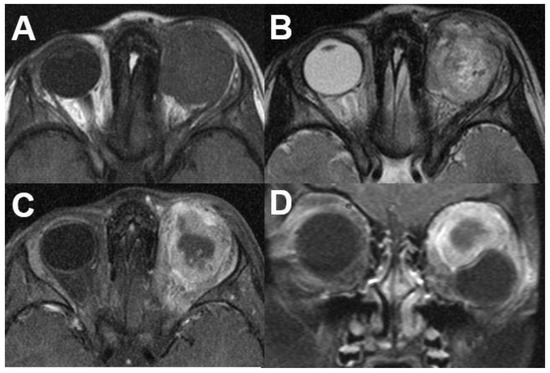

3.1.2. Uveal Melanoma

3.6.1. Metastasis